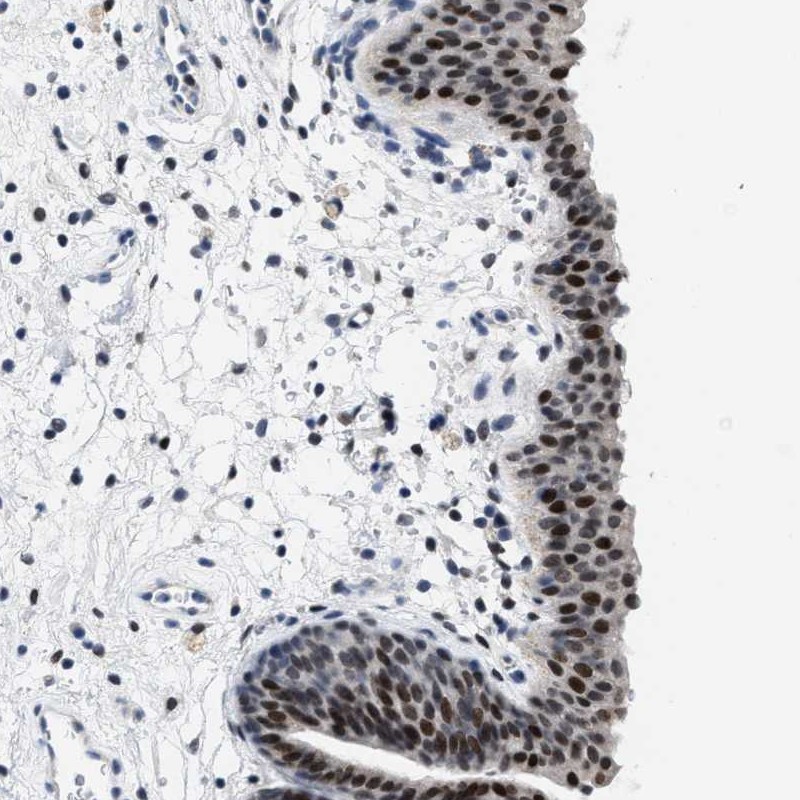

Immunohistochemical staining of human urinary bladder shows strong nuclear positivity.